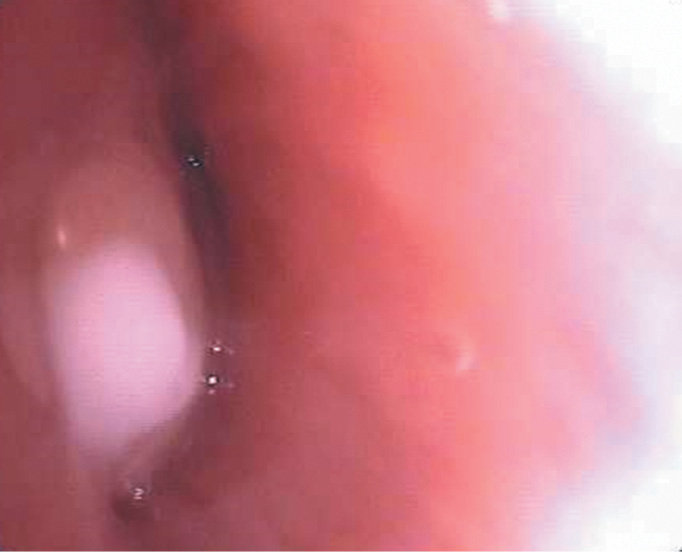

21.05 проведена видеобронхоскопия под общей анестезией: выявлено образование и обтурация бронха В3 справа. Эндоскопическая картина похожа на туберкулезное поражение лимфатического узла (рис. 4).

Рис. 4. Видеобронхоскопия ребенка Н., 8 лет 7 мес., 21.05. Образование и обтурация бронха В3 справа. Эндоскопическая картина похожа на туберкулезное поражение лимфатического узла

Fig. 4. Videobronchoscopy of the child N., 8 years 7 months, 21.05. Formation and obturation of bronchus v3 on the right. The endoscopic picture is similar to the tuberculous lesion of the lymph node